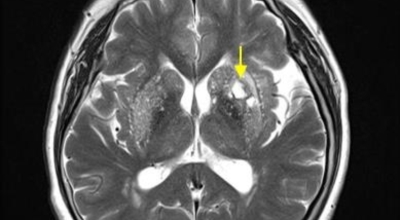

파킨슨병이라는 것은, 퇴행성 뇌 질환으로 알츠하이머, 치매 다음으로 자주 나타나는 뇌 연관 질병으로 1817년 영국 병리학자 파킨슨이 보고 해서 그의 이름을 따서 병의 이름이 결정되었다고 합니다.파킨슨병에 걸릴 경우 일반적으로 40세 이후로 첫 증상이 나타나고 50세에 가장 많이 발생한는 것으로 알려져 있고 30세 이전에는 아주 드물지만 유전적으로 나타나는 경우도 있다고 합니다.

파킨슨병은 도파민 분비 신경 세포의 소실로 발생하는 질환으로 알려져 있는데요 도파민이란 뇌의 신경세포에서 만들어지는 물질로 세포와 세포 간의 신호를 전달하는데 이용되는 신경 전달 물질 중 한가지로 이 도파민이 감소함에 따라 파킨슨병이 걸린다고 하는데 이 도파민 세포가 떨어지는 이유는 아직 정확히 밝혀지지 않았다고 합니다.